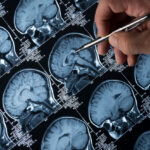

A team of researchers at the University of California, Los Angeles (UCLA) has identified a gene that plays a key role in the growth of glioblastoma multiforme (GBM), a rare and lethal brain cancer that has no known cure. The new research suggests that focusing on this gene, called P300, could help provide a therapeutic target for GBM, which is highly resistant to standard chemotherapy.

According to the National Brain Tumor Society, GBM can affect men, women, and children of all ages and backgrounds. Although rare, it accounts for nearly half of all primary malignant brain tumors, the five-year survival rate from diagnosis is only 6.8%, and “the average length of survival is measured in months,” according to a UCLA press release. Beau Biden, former Attorney General of Delaware and the eldest son of President Joe Biden, and U.S. Senators Edward “Ted” Kennedy and John McCain all lost their lives to this type of aggressive cancer.

While examining P300, the researchers found that it “enables cancer cells that have been damaged by radiation therapy to recover by rearranging DNA and initiating a molecular mechanism that refortifies tumor cells for growth and survival.” By blocking the gene, the ability to set that process in motion was disrupted.